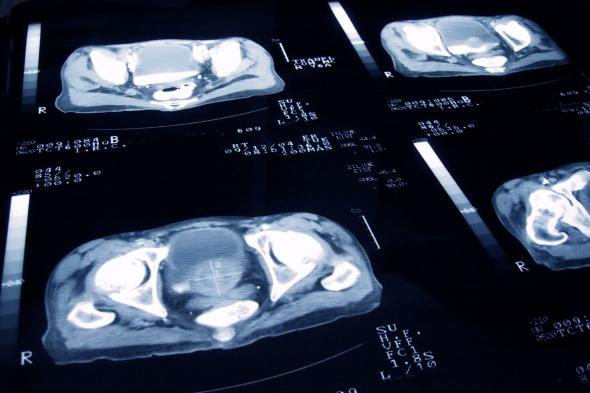

Imagen de unos escáneres de cáncer de próstataGetty Images

El cáncer de próstata es el más común entre los hombres en España, por eso en los últimos años se han dedicado recursos y tiempo para intentar encontrar métodos de diagnóstico más efectivos y tempranos, que permitan aplicar tratamientos más adecuados para eliminar la enfermedad.

Según los expertos, el problema de los malos diagnósticos de cáncer de próstata es que suelen producirse cuando el cáncer está bastante avanzado y es más difícil de tratar, mientras que si la detección fuera temprana los tratamientos serían más efectivos.